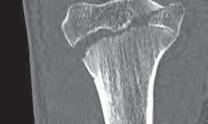

Podział złamań kości rosnących, tzw. złamań nasadowych: A – schematyczne przedstawienie klasyfikacji złamań; B – SH I (RTG, widok z przodu i z boku); C – SH II (RTG, widok z przodu i z boku); D – SH II (TK, widok z boku); E – SH III (RTG, widok z przodu i z boku); F – SH IV (RTG, widok z przodu i z boku); G – SH V (RTG, widok z przodu i z boku).

Dalszy podział jest specyficzny wyłącznie dla kości rosnących i dotyczy tzw. złamań nasadowych. Został opublikowany przez Saltera i Harrisa i jest to najważniejszy podział złamań kości rosnących (ryc. 6.3 A–G).